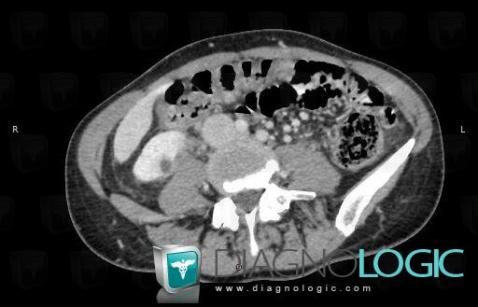

Abscess, Kidney, CT

Here is the specific information in the key image above:

- Diagnosis Abscess, Location(s) Kidney, with gamuts Exophytic renal mass, Solid renal mass, Hypervacular renal mass